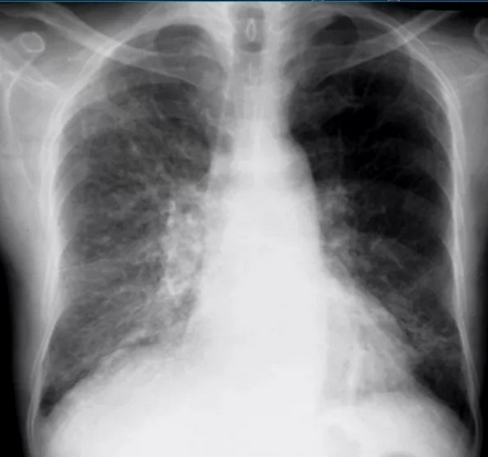

Магнитно-резонансная томография (МРТ):один из самых эффективных методов диагностики заболеваний